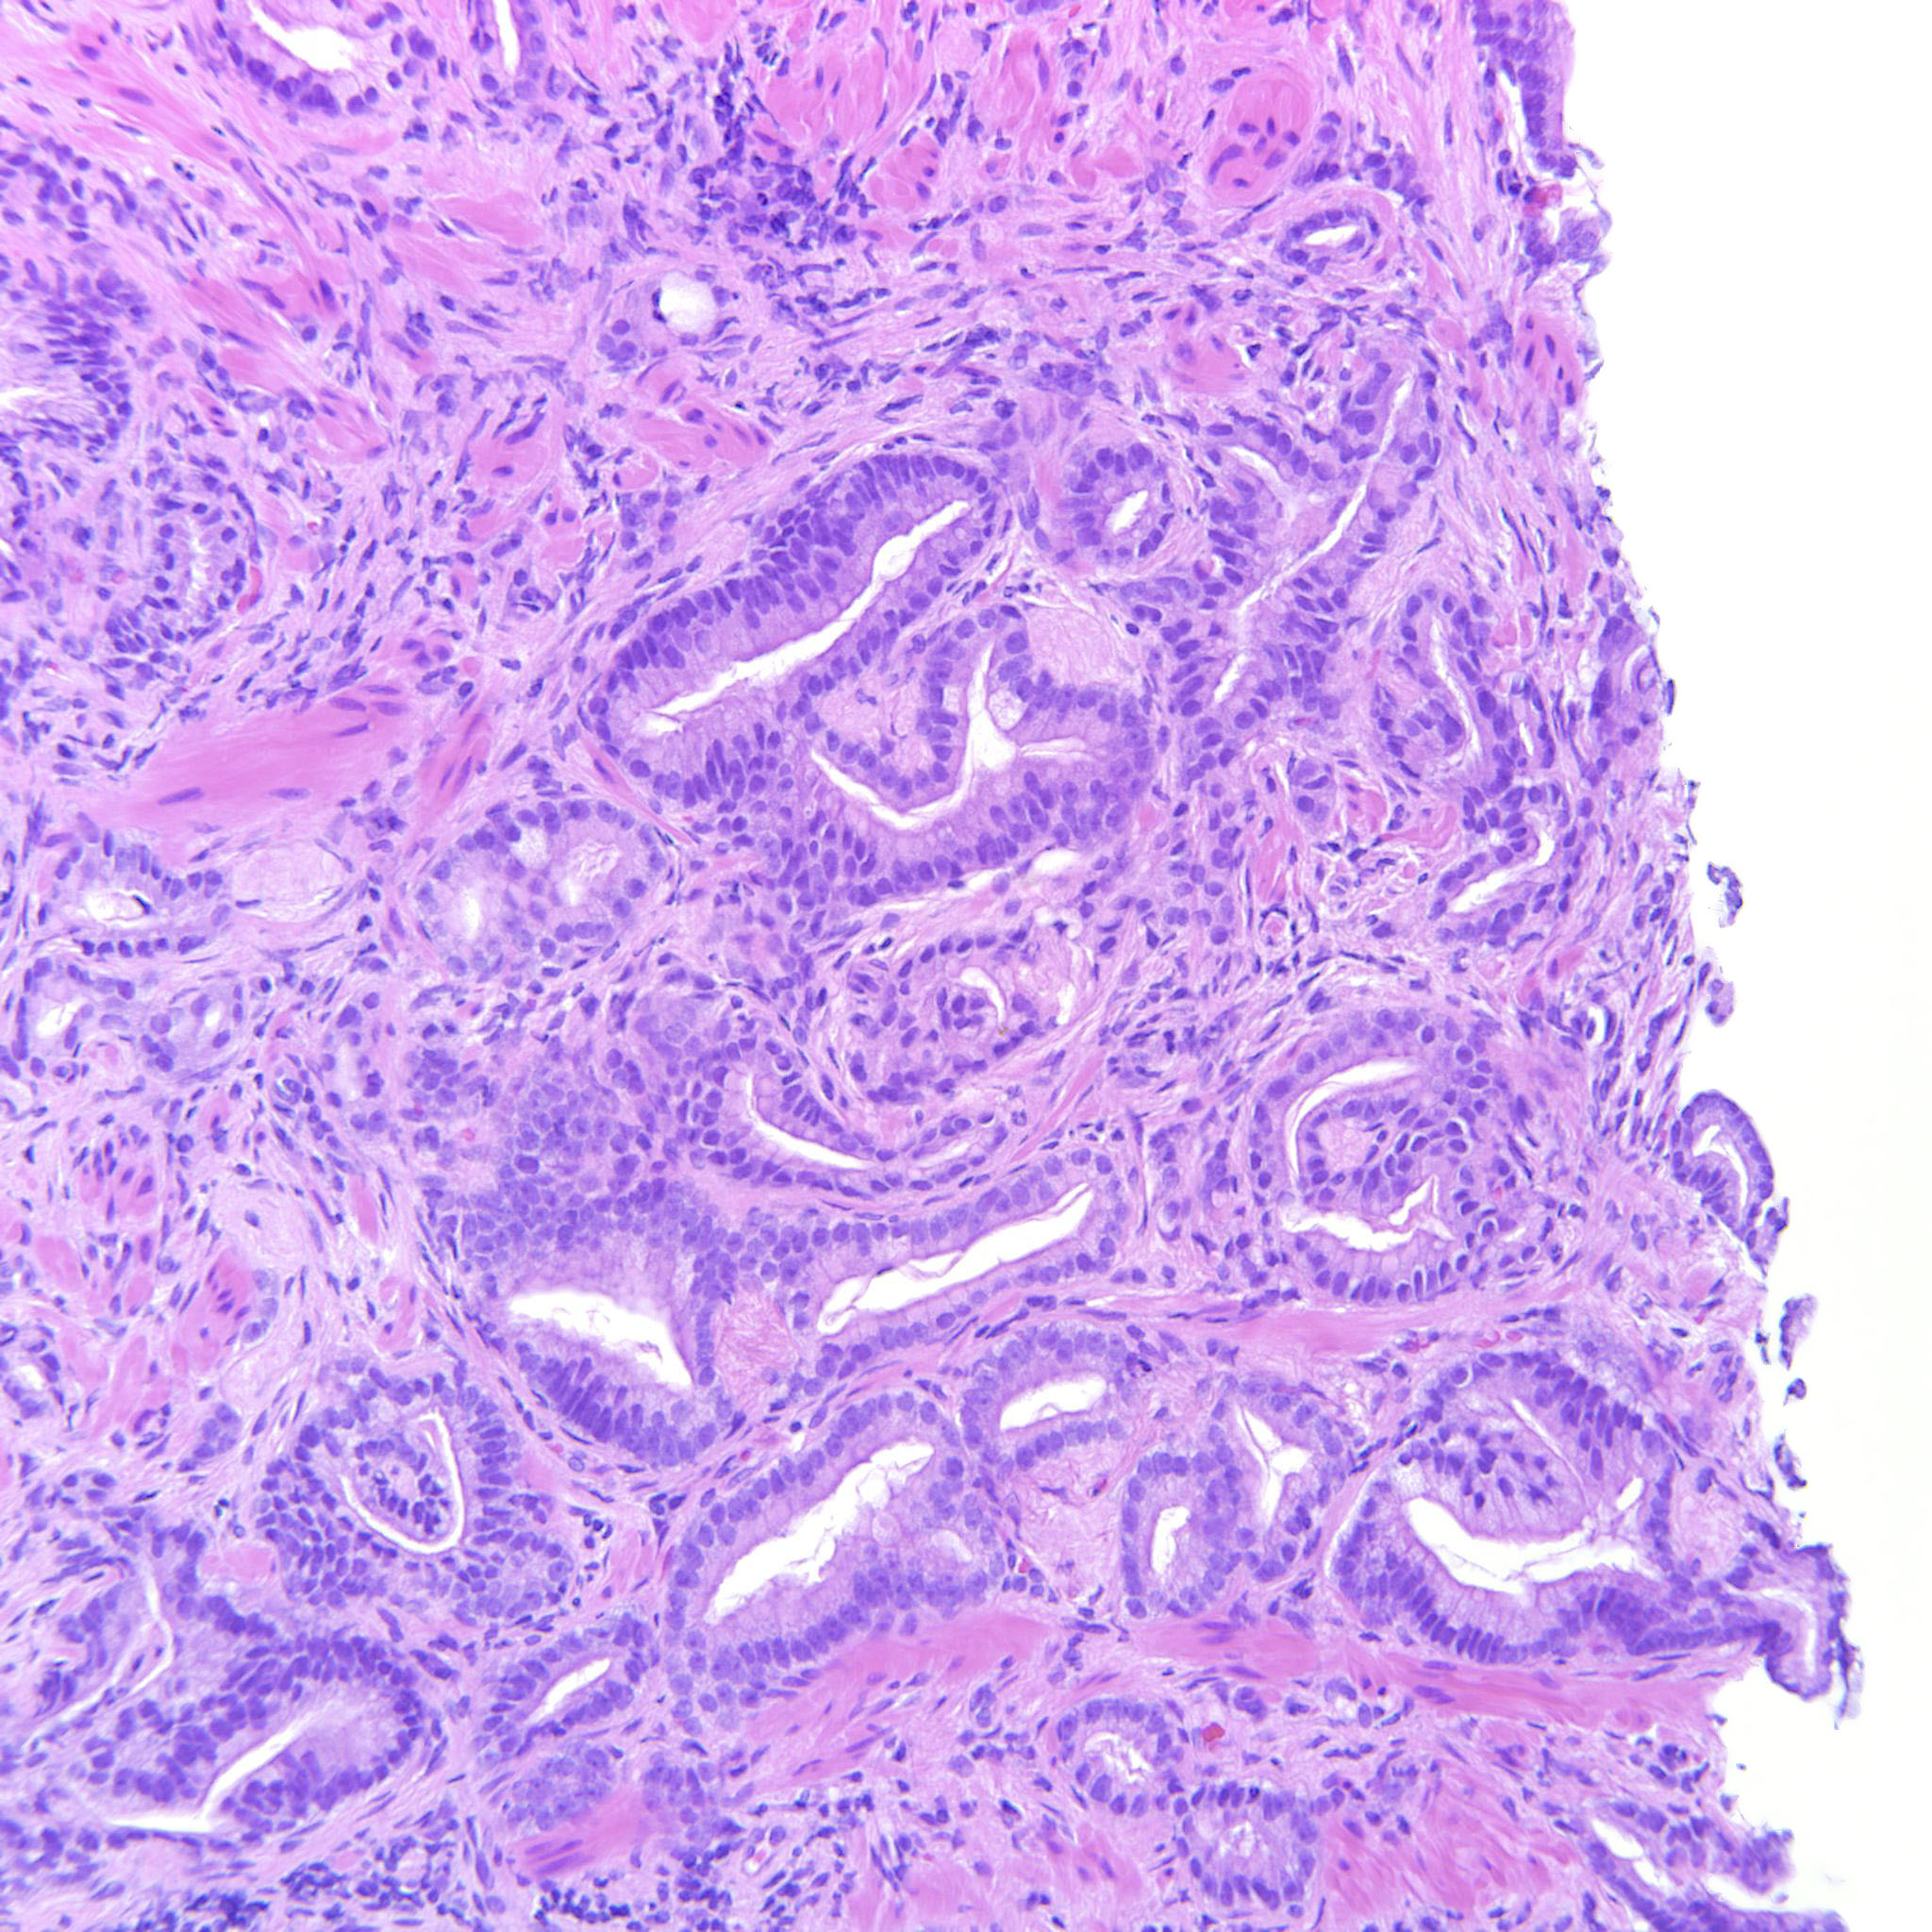

Prostate cancer grading

Case ID: 516